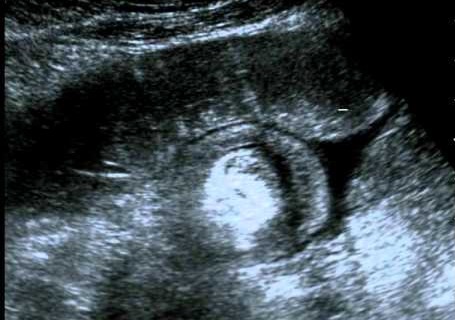

Se realiza una ecografía abdominal, que es informada como:

• Imagen de rosquilla en la fosa iliaca derecha, con imagen de pseudomasa en su interior que se extiende hasta el colon ascendente. El resto del marco cólico se encuentra colapsado, con un grosor de pared normal.

• El íleon distal está distendido y con abundante contenido ecogénico.

• Mínima cantidad de líquido libre intraperitoneal.

Se realiza una desinvaginación con enema de suero salino fisiológico, sin complicaciones. Continúa observándose la imagen de pseudomasa.